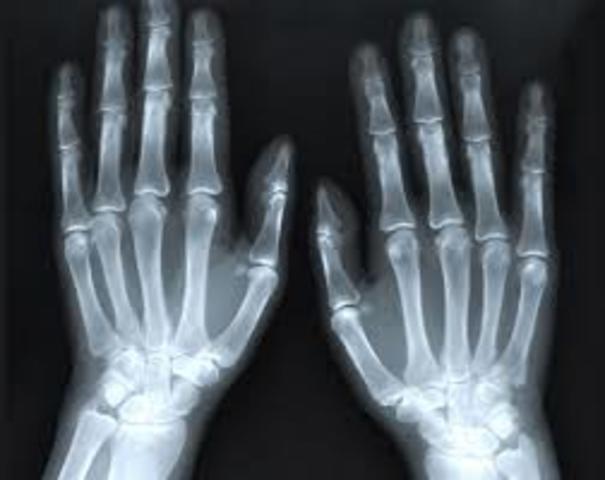

• Los Rayos X

Los Rayos X

Wilhelm Röntgen descubre los Rayos X, logrando fijar por primera vez en una superficie transparente la imagen de los huesos de una mano. Este fue un gran avance en la medicina